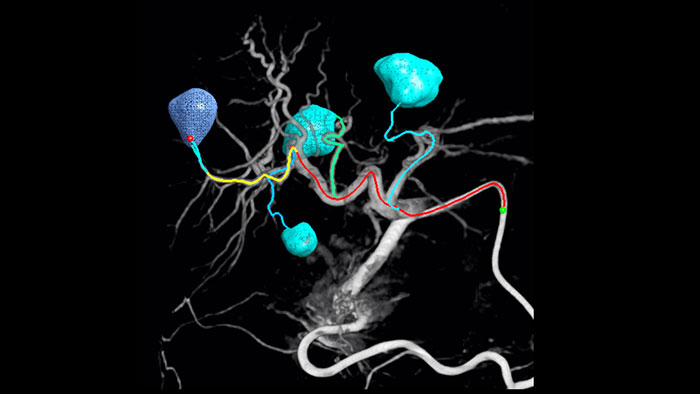

L’adoption de techniques de chimio/radioembolisation telles que la chimio-embolisation transartérielle et SIRT entraîne un besoin de standardisation et d’efficacité. Cas après cas, vous devez localiser de manière fiable et cohérente la ou les tumeurs, identifier tous les vaisseaux nourriciers et planifier/exécuter l’approche interventionnelle appropriée. Notre solution de détection automatique des vaisseaux nourriciers améliore de manière significative la détection des artères nourricières par rapport à l’utilisation de la tomographie à faisceau conique seule. EmboGuide vous aide à maximiser l’efficacité de vos procédures de chimio-embolisation transartérielle en améliorant votre sensibilité, en réduisant les faux positifs et en maximisant la concordance entre les lecteurs .1

La capacité de détecter et de différencier les nodules hépatiques et d’identifier les minuscules vaisseaux nourriciers est essentielle pour déterminer le traitement approprié. La navigation vers la région d’intérêt en atteignant tous les vaisseaux nourriciers, tout en restant sélective par rapport à la lésion, augmente les chances de succès. La confirmation de la fin et du succès du traitement alors que le patient est encore sur la table renforce la confiance dans les résultats cliniques.